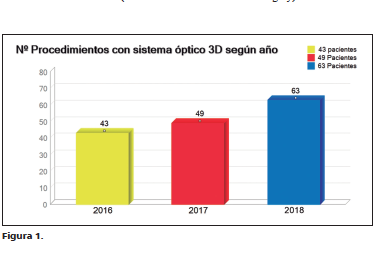

Italo Braghetto M, Fernando Marchant G, Mario Abedrapo M, Jaime Castillo K, Enrique Lanzarini S, Juan Carlos Diaz J, Rodrigo Azolaz F, Rodrigo Ledezma R, Manuel Figueroa-Giralt

|

|

|